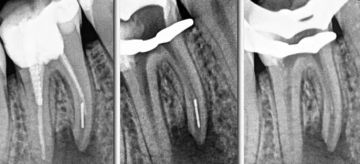

Микроскопная эндодонтия. Методика безопасного извлечения фрагментов сломанных эндодонтических инструментов из корневых каналов

– Демонстрация способов и основных этапов по извлечению эндодонтических инструментов из корневых каналов с применением дентального микроскопа из устьевой, средней и апикальной трети на основании 70 клинических случаев

– Проведение процедуры извлечения поломанного инструмента, в зависимости от местоположения в системе корневого канала

– Демонстрация способов и основных этапов по извлечению эндодонтических инструментов из корневых каналов с применением дентального микроскопа из средней и апикальной трети лектором и работа участников курса на моделях, которые подготовили самостоятельно